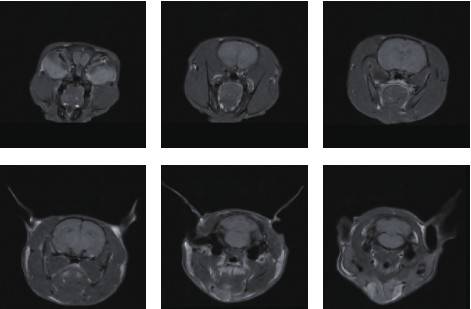

小鼠頭部成像

皮下腫瘤成像